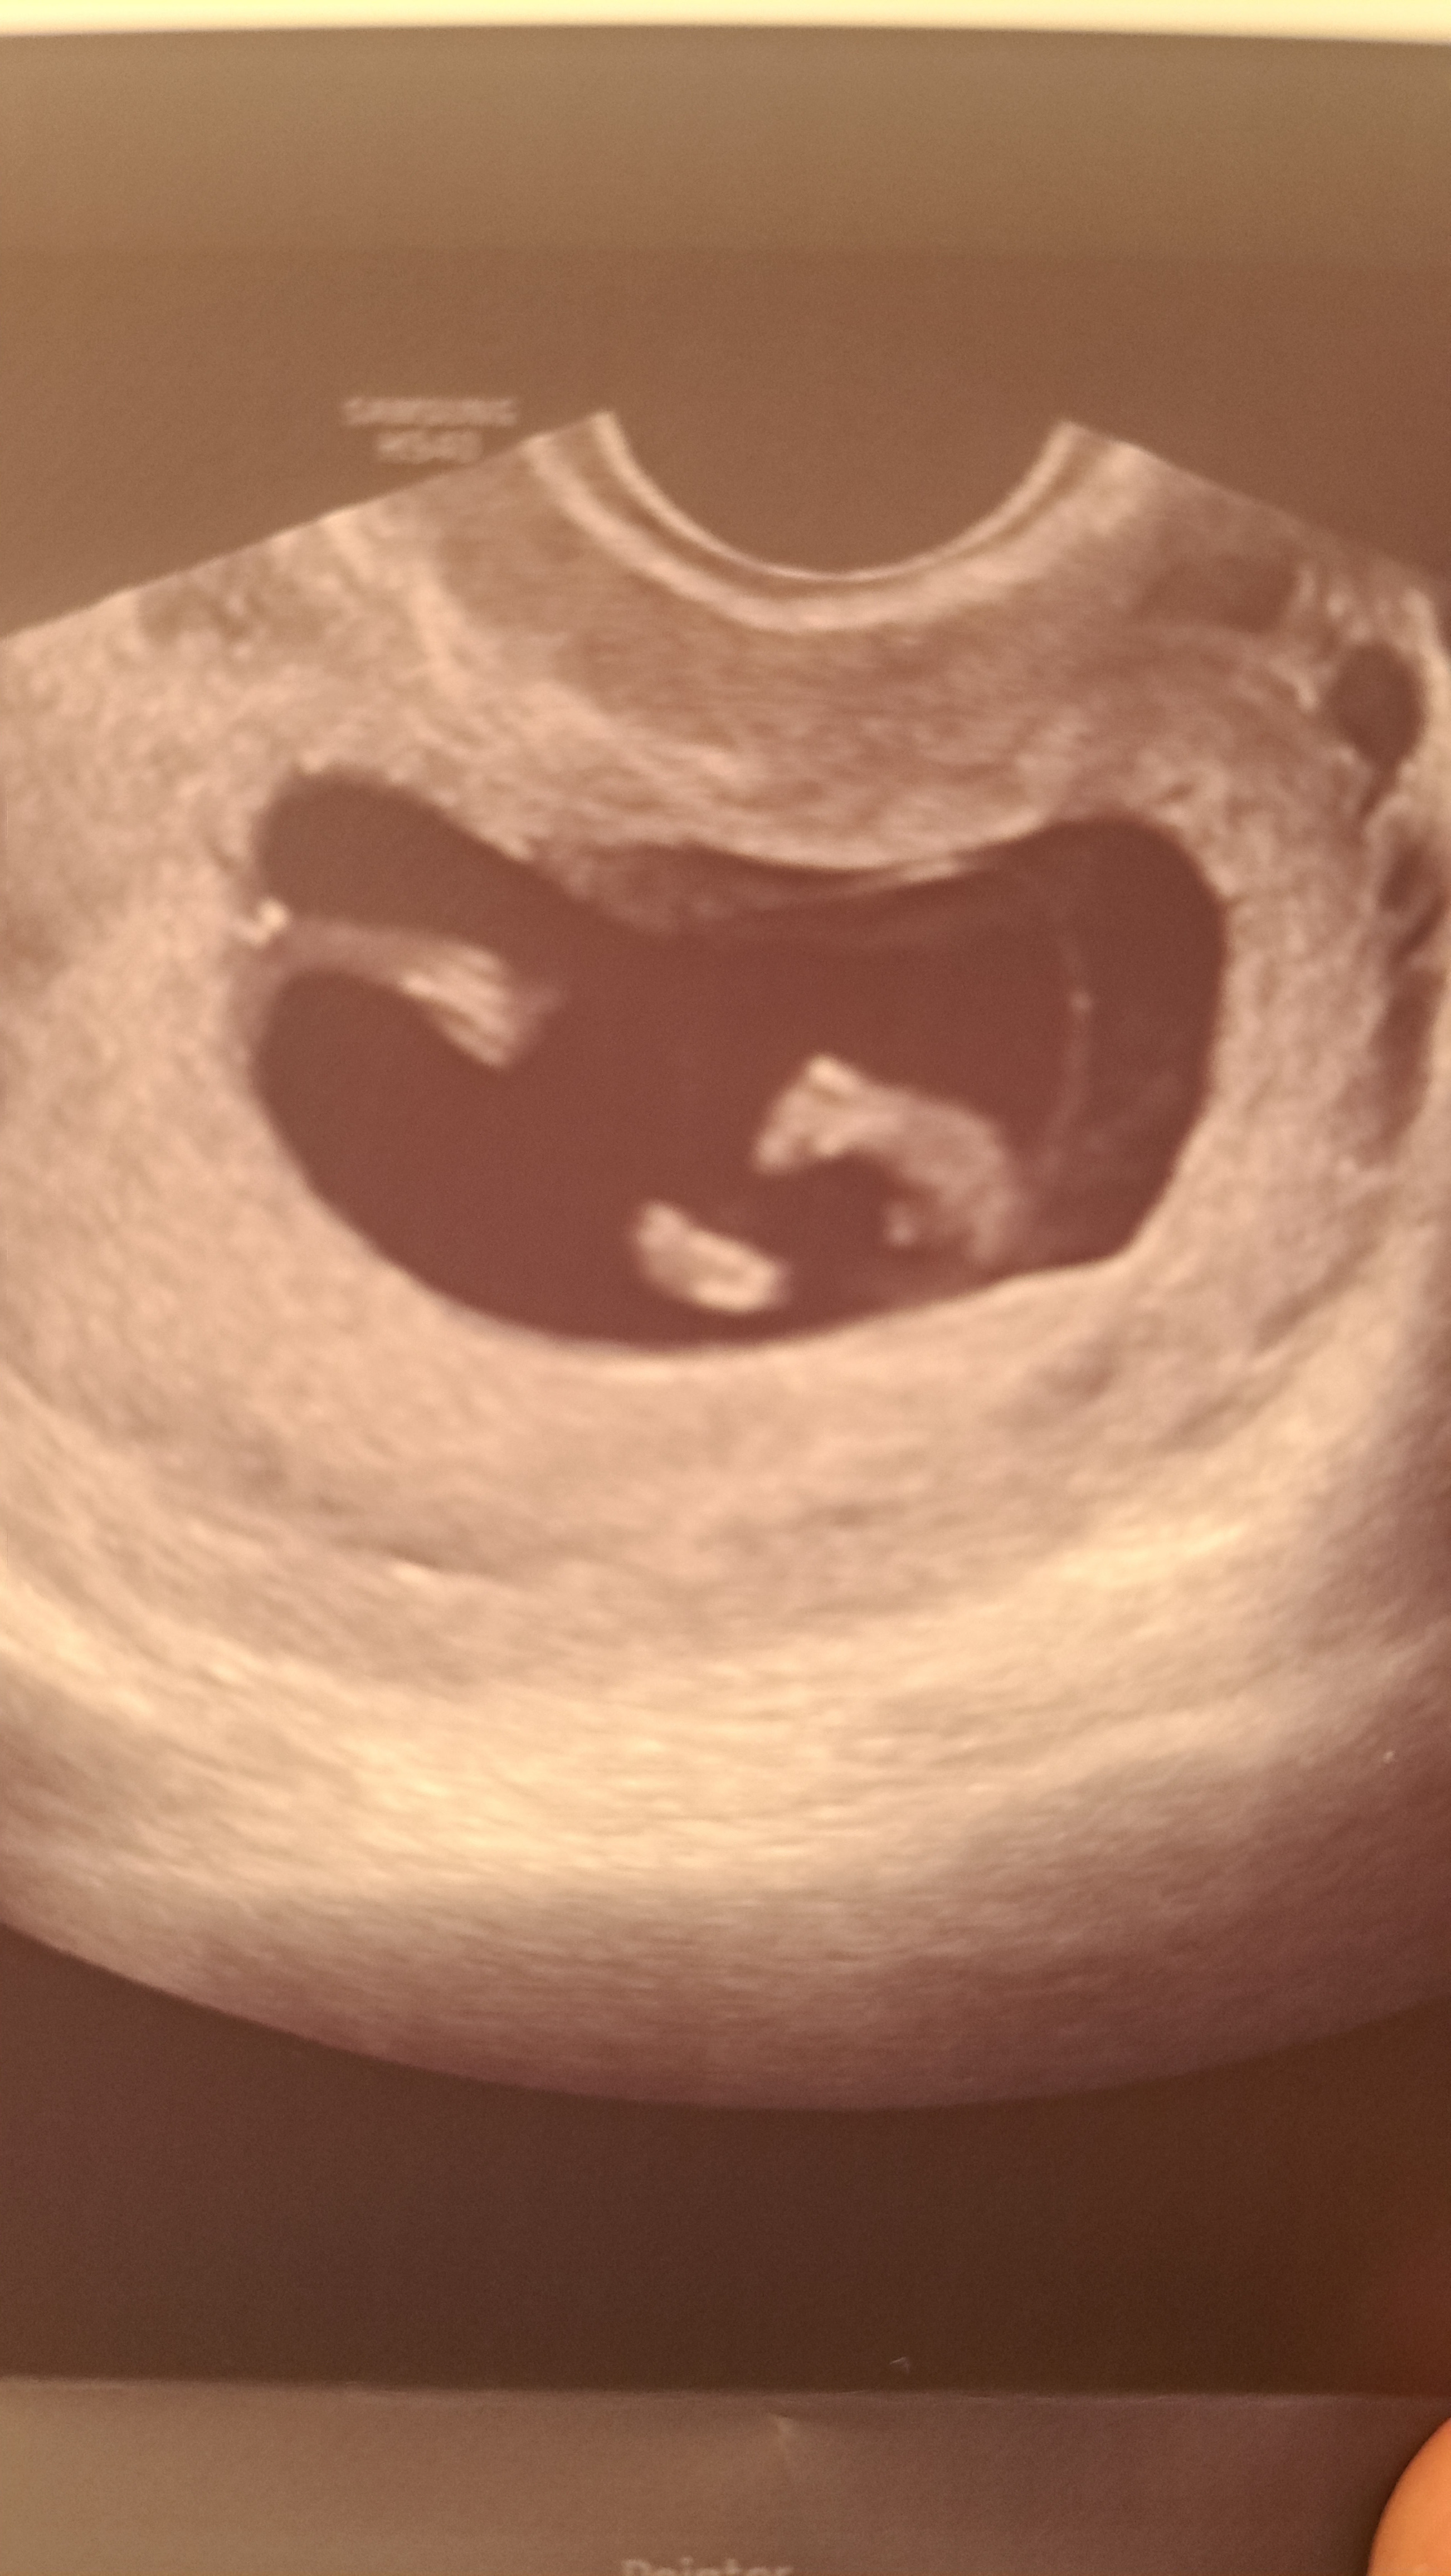

Witajcie, jestem w 11t2d czy widzmy tu juz plec dziecka?

Ja widze nozki o ile to nozki ![]()

Lekarz zasugerowal chlopca wiec sie zastawiam czy to w srodku odstajace to wzial za siusiaka

ja tutaj widze nozki i możliwe że przyrodzenie ale to może być dużo innych rzeczy lepiej poczekać jeszcze trochę na dokładniejszy obraz

To usg z wizyty, za tydzien mam prenatalne

zaskoczyl mnie doktor tak szybka ocena plci, nie myslalam ze moze byc juz wiadomo, i ze to przyrodzenie

jesli to jest to moze byc juz takie duze… usg mialam jeszcze przezpochwowe